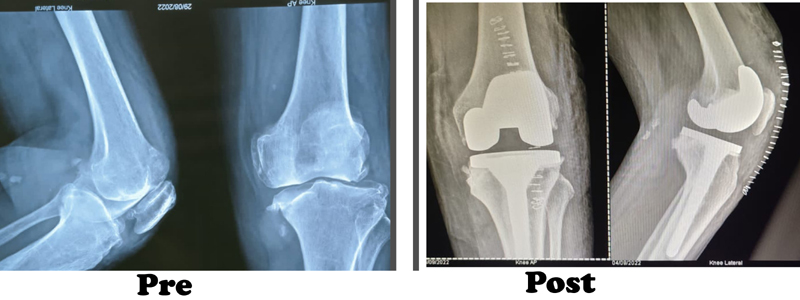

During the knee replacement surgery, the worn out surface (cartilage) of the joint is removed and is capped with implants called as endo-prosthesis. The femur and tibial sides are metal backed and in between there is polyethylene ‘insert’. The patella may or may not be replaced, depending upon the surgeon preference and condition of patellar cartilage.

The surgeon will make an incision on the top of your knee in order to expose the damaged area of your joint. The standard incision size can be as long as 10 inches, but a minimally invasive procedure can result in incisions as short as 6 inches. During the operation, the surgeon moves your kneecap aside and cuts away damaged bone and cartilage, which are then replaced with new metal and plastic components. The components combine to form a synthetic (but biologically compatible) joint that mimics the movement of your natural knee. Most knee replacement procedures take 30min - 1 hour to complete.